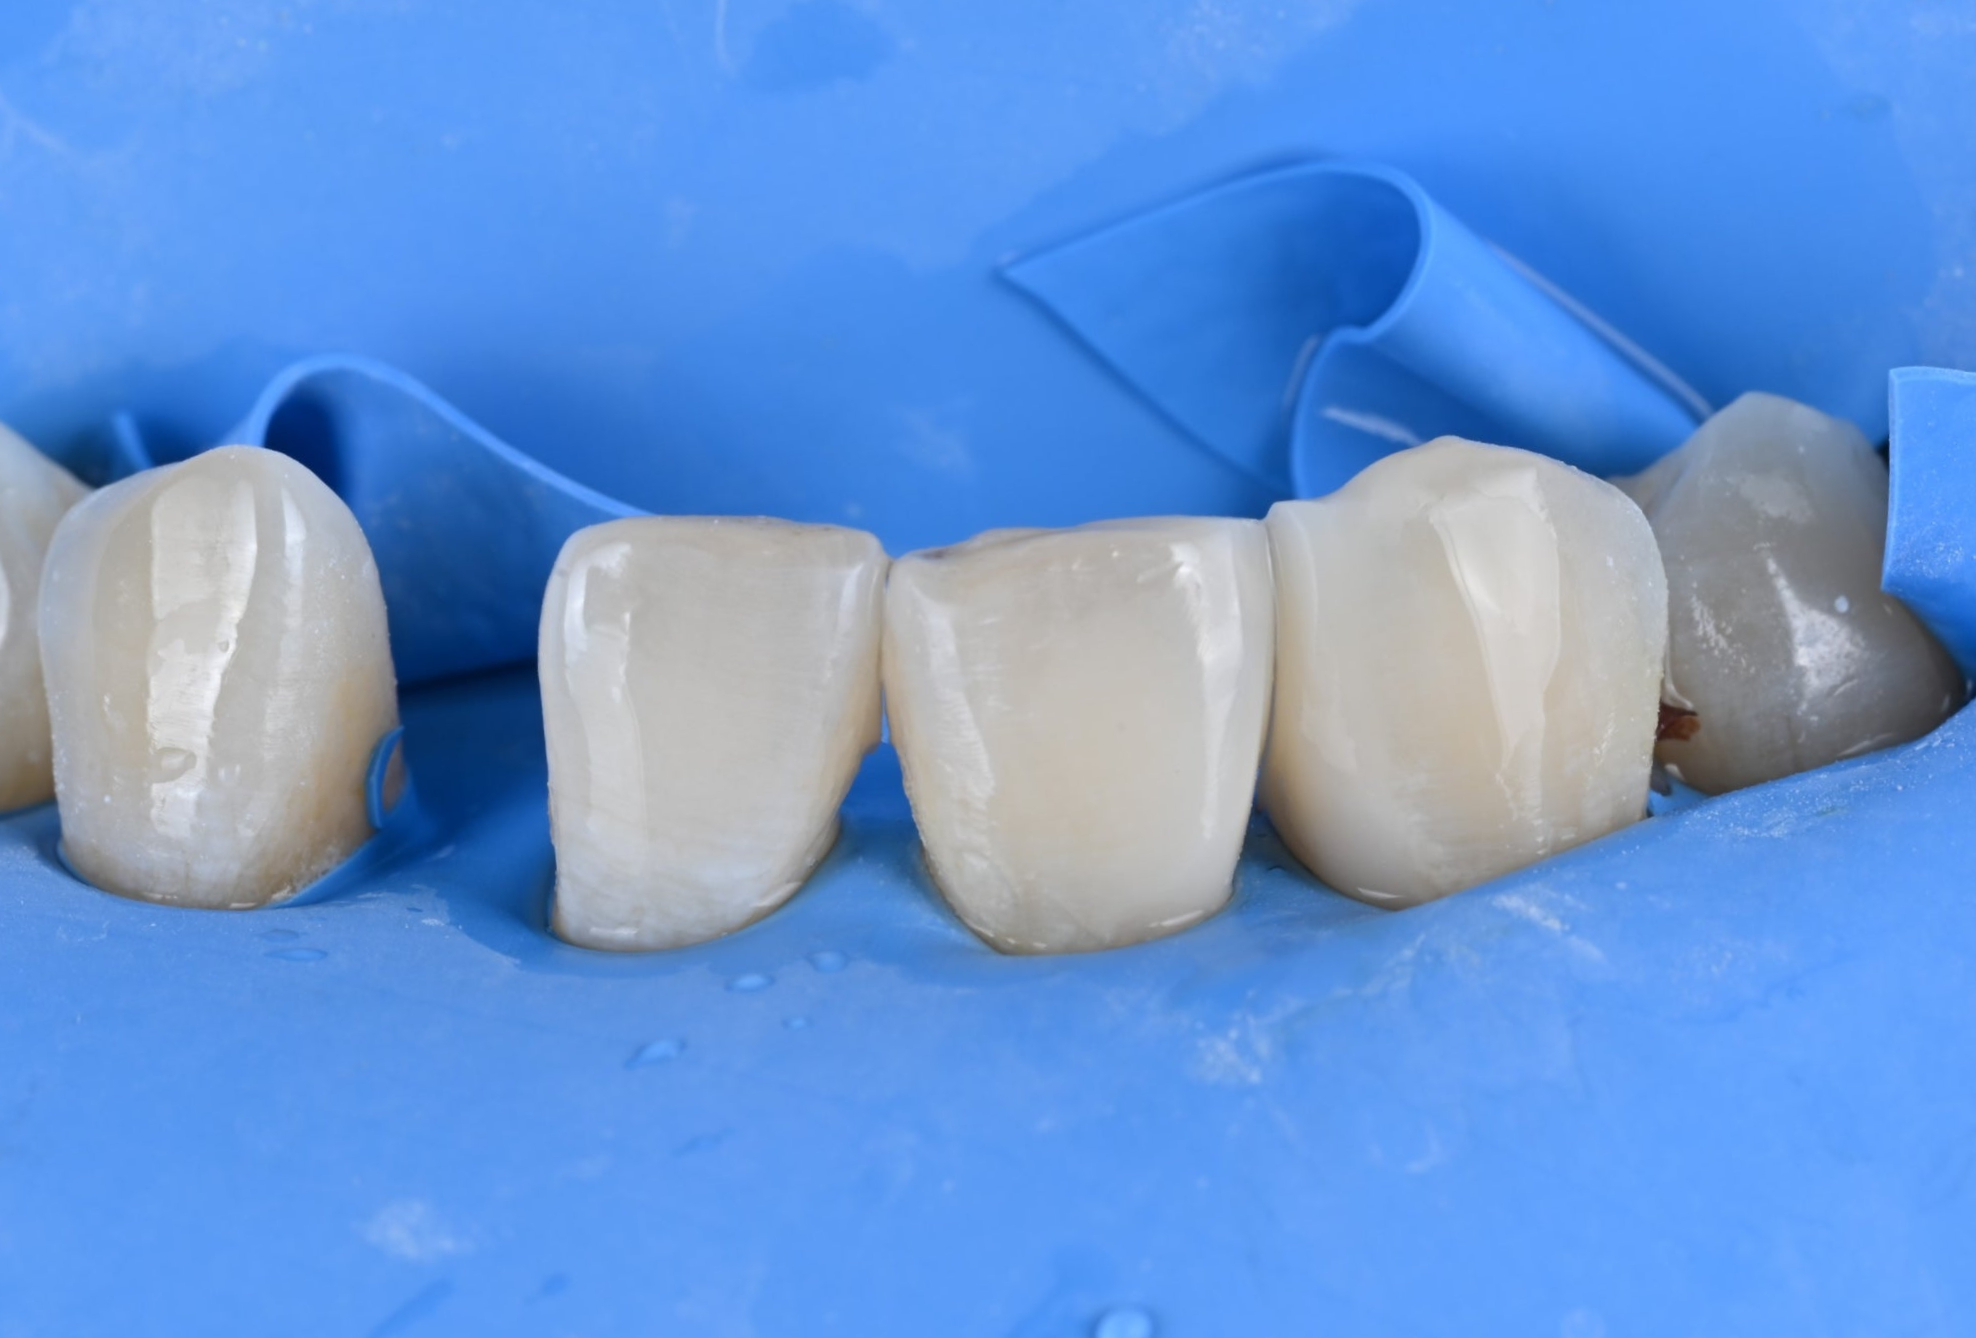

26.03.19 레진 치료를 위한 러버댐 장착

26.03.19 바이오클리어를 이용한 레진 수복

1) 러버댐 장착

레진 수복과 브릿지 접착 모든 과정에서

러버댐을 사용하여 입안의 습기를

완벽히 차단했습니다.

26.04.02 메릴랜드 브릿지 접착 준비